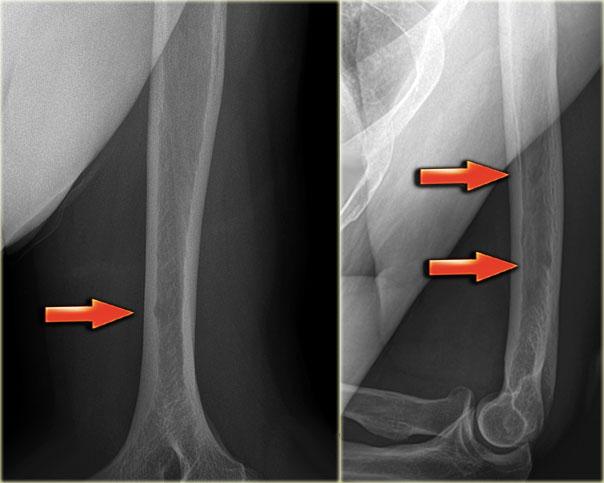

SBC: well-defined osteolytic lesion without expansion of the proximal meta-diaphysis of the humerus with pathologic fracture

Solitary Bone Cyst

Nang xương đơn độc, còn được gọi là nang xương đơn buồng, là một nang xương thực sự.

Nhiều tổn thương tiêu xương giới hạn rõ thường được gọi là dạng nang, nhưng đây là cách gọi không chính xác.

Nang xương đơn độc thường biểu hiện bằng gãy xương.

Đôi khi có thể thấy hình ảnh mảnh xương gãy rơi xuống (fallen fragment).

Vị trí hay gặp: đầu trên xương cánh tay và xương đùi.

Thường ít giãn nở hơn so với nang xương phình mạch.

Chẩn đoán phân biệt: nang xương phình mạch, loạn sản xơ dạng nang.

Nang xương đơn độc có thể di chuyển từ vùng hành xương đến thân xương trong quá trình phát triển của xương.

Discriminators:

- Must be under age 30.

- Must be centric